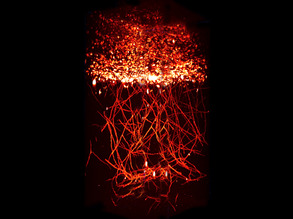

Brain Veins

06